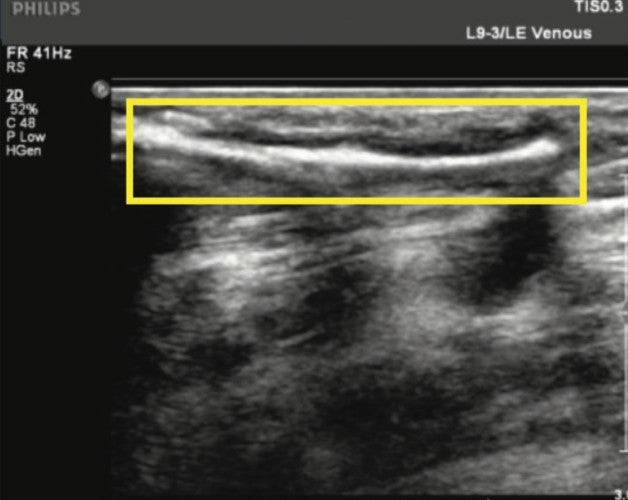

Figure 3. Mid-calf GSV perforator pre-Varithena treatment.

Pre-treatment: Color-flow Doppler ultrasound was performed on the left lower extremity and the varicose veins were mapped. Two access points were chosen in the left lower leg, mid-calf and distal calf.